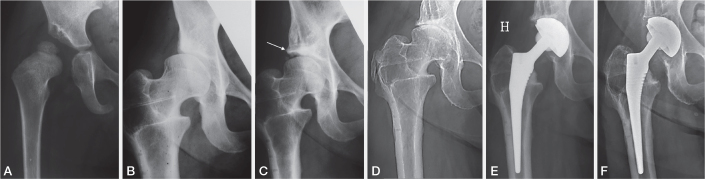

Background and purpose:  Our aim was to compare age at time of total hip arthroplasty (THA) and the THA survival time in patients with late-detected developmental dislocation and dysplasia of the hip (DDH) treated with traction in childhood who had either undergone acetabular shelf operation due to persistent DDH, or no previous acetabular surgery but persistent DDH, or no previous acetabular surgery and CE angle ≥ 18°.

Methods:  112 patients (97 females; 144 hips) with late-detected DDH who had undergone THA were studied. 70 hips had undergone a modified Spitzy procedure (SA group) at the age of 8-33 years. They were compared with 2 groups that had not undergone previous pelvic surgery: a "Dysplasia" group with residual (persistent) acetabular dysplasia (CE angle < 18°, 33 hips) and a "Normal" group with no residual dysplasia (37 hips). We analyzed age at THA and the survival rate (percentage of THAs not having undergone revision).

Results:  Mean patient age at THA did not differ between the SA group (52 years) and the Dysplasia group (49 years; P = 0.1). 11 THAs had been revised in the SA group and 9 in the Dysplasia group. Kaplan-Meier analysis showed 20-year survival rates of 88% in the SA group and 68% in the Dysplasia group. The estimated survival time of THA was significantly higher in the SA group than in the Dysplasia group (29.4 and 19.8 years; P = 0.01). Mean age at THA was significantly lower in the Dysplasia group than in the Normal group (49 and 55 years), but there was no significant difference between these groups in estimated survival time of THA.

Conclusion:  A previous acetabular shelf operation in patients with persistent DDH does not appear to delay age at THA but THA had better survival rate.